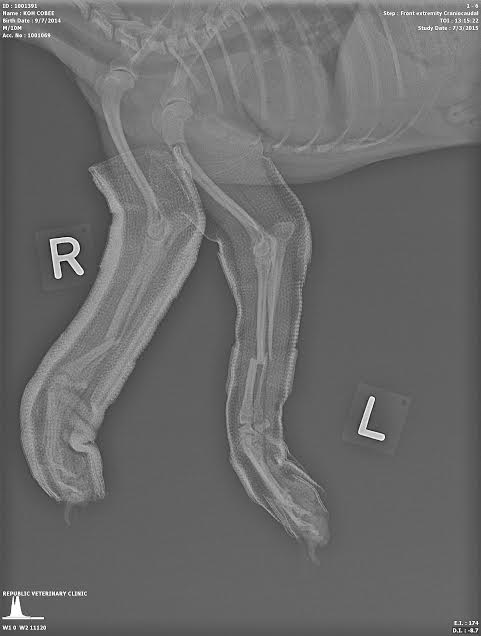

Occasionally closed reduction of closed fractures is not possible because of delay in attempting the reduction or because of interposed soft tissue. Sometimes open reduction of closed fractures may be performed without internal fixation, especially in fractures that are relatively transverse. See X-ray of the distal 1/3 radial and ulnar fracture of left foot in this case